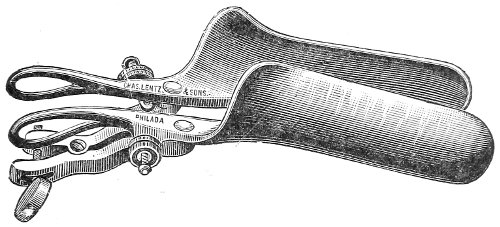

The Vaginal Speculum.—The speculum is an instrument through which a visual examination is made of the vagina, the external os uteri, and the vaginal cervix. A 29 great number of specula have been invented. At the present day the best two instruments of this class are the bivalve speculum, such as Goodell’s (Fig. 6), and the duck-bill speculum (Fig. 7), or perineal retractor, invented by Sims.

Fig. 6.—Goodell’s speculum.

The bivalve speculum is introduced with the woman upon her back, in the dorso-sacral position already described. The vulva and the vagina should be cleaned. The speculum should be warmed by placing it in hot water, and should then be lubricated with the soap solution or with vaseline. It should be introduced with the blades closed and the plane of the blades lying not exactly 30 in the median sagittal plane of the body, but inclined at a small acute angle to this plane, one edge of the speculum being directed toward either vaginal sulcus. The instrument is passed into the vagina toward the position in which, by a previous digital examination, the vaginal cervix had been found to lie. The instrument is then turned with the handles toward either thigh, so that the blades become parallel to the anterior and posterior vaginal walls, in order that, when separated, they will open the vaginal slit. The handles are brought together and the blades opened. When the vaginal cervix comes well into view the blades are fixed in place by the screws (Fig. 9).

Fig. 9.—Goodell’s speculum in position.

In some cases, where the cervix points well forward or well backward, it may be readily brought into view through the speculum by catching it with a tenaculum.

By means of the bivalve speculum we are able to make a partial inspection of the vaginal walls, an imperfect inspection of the vaginal vault, and a good inspection of the vaginal cervix and the external os. Applications 31 can be made to the cervix, but none of the minor operations of gynecology can be performed through this speculum.